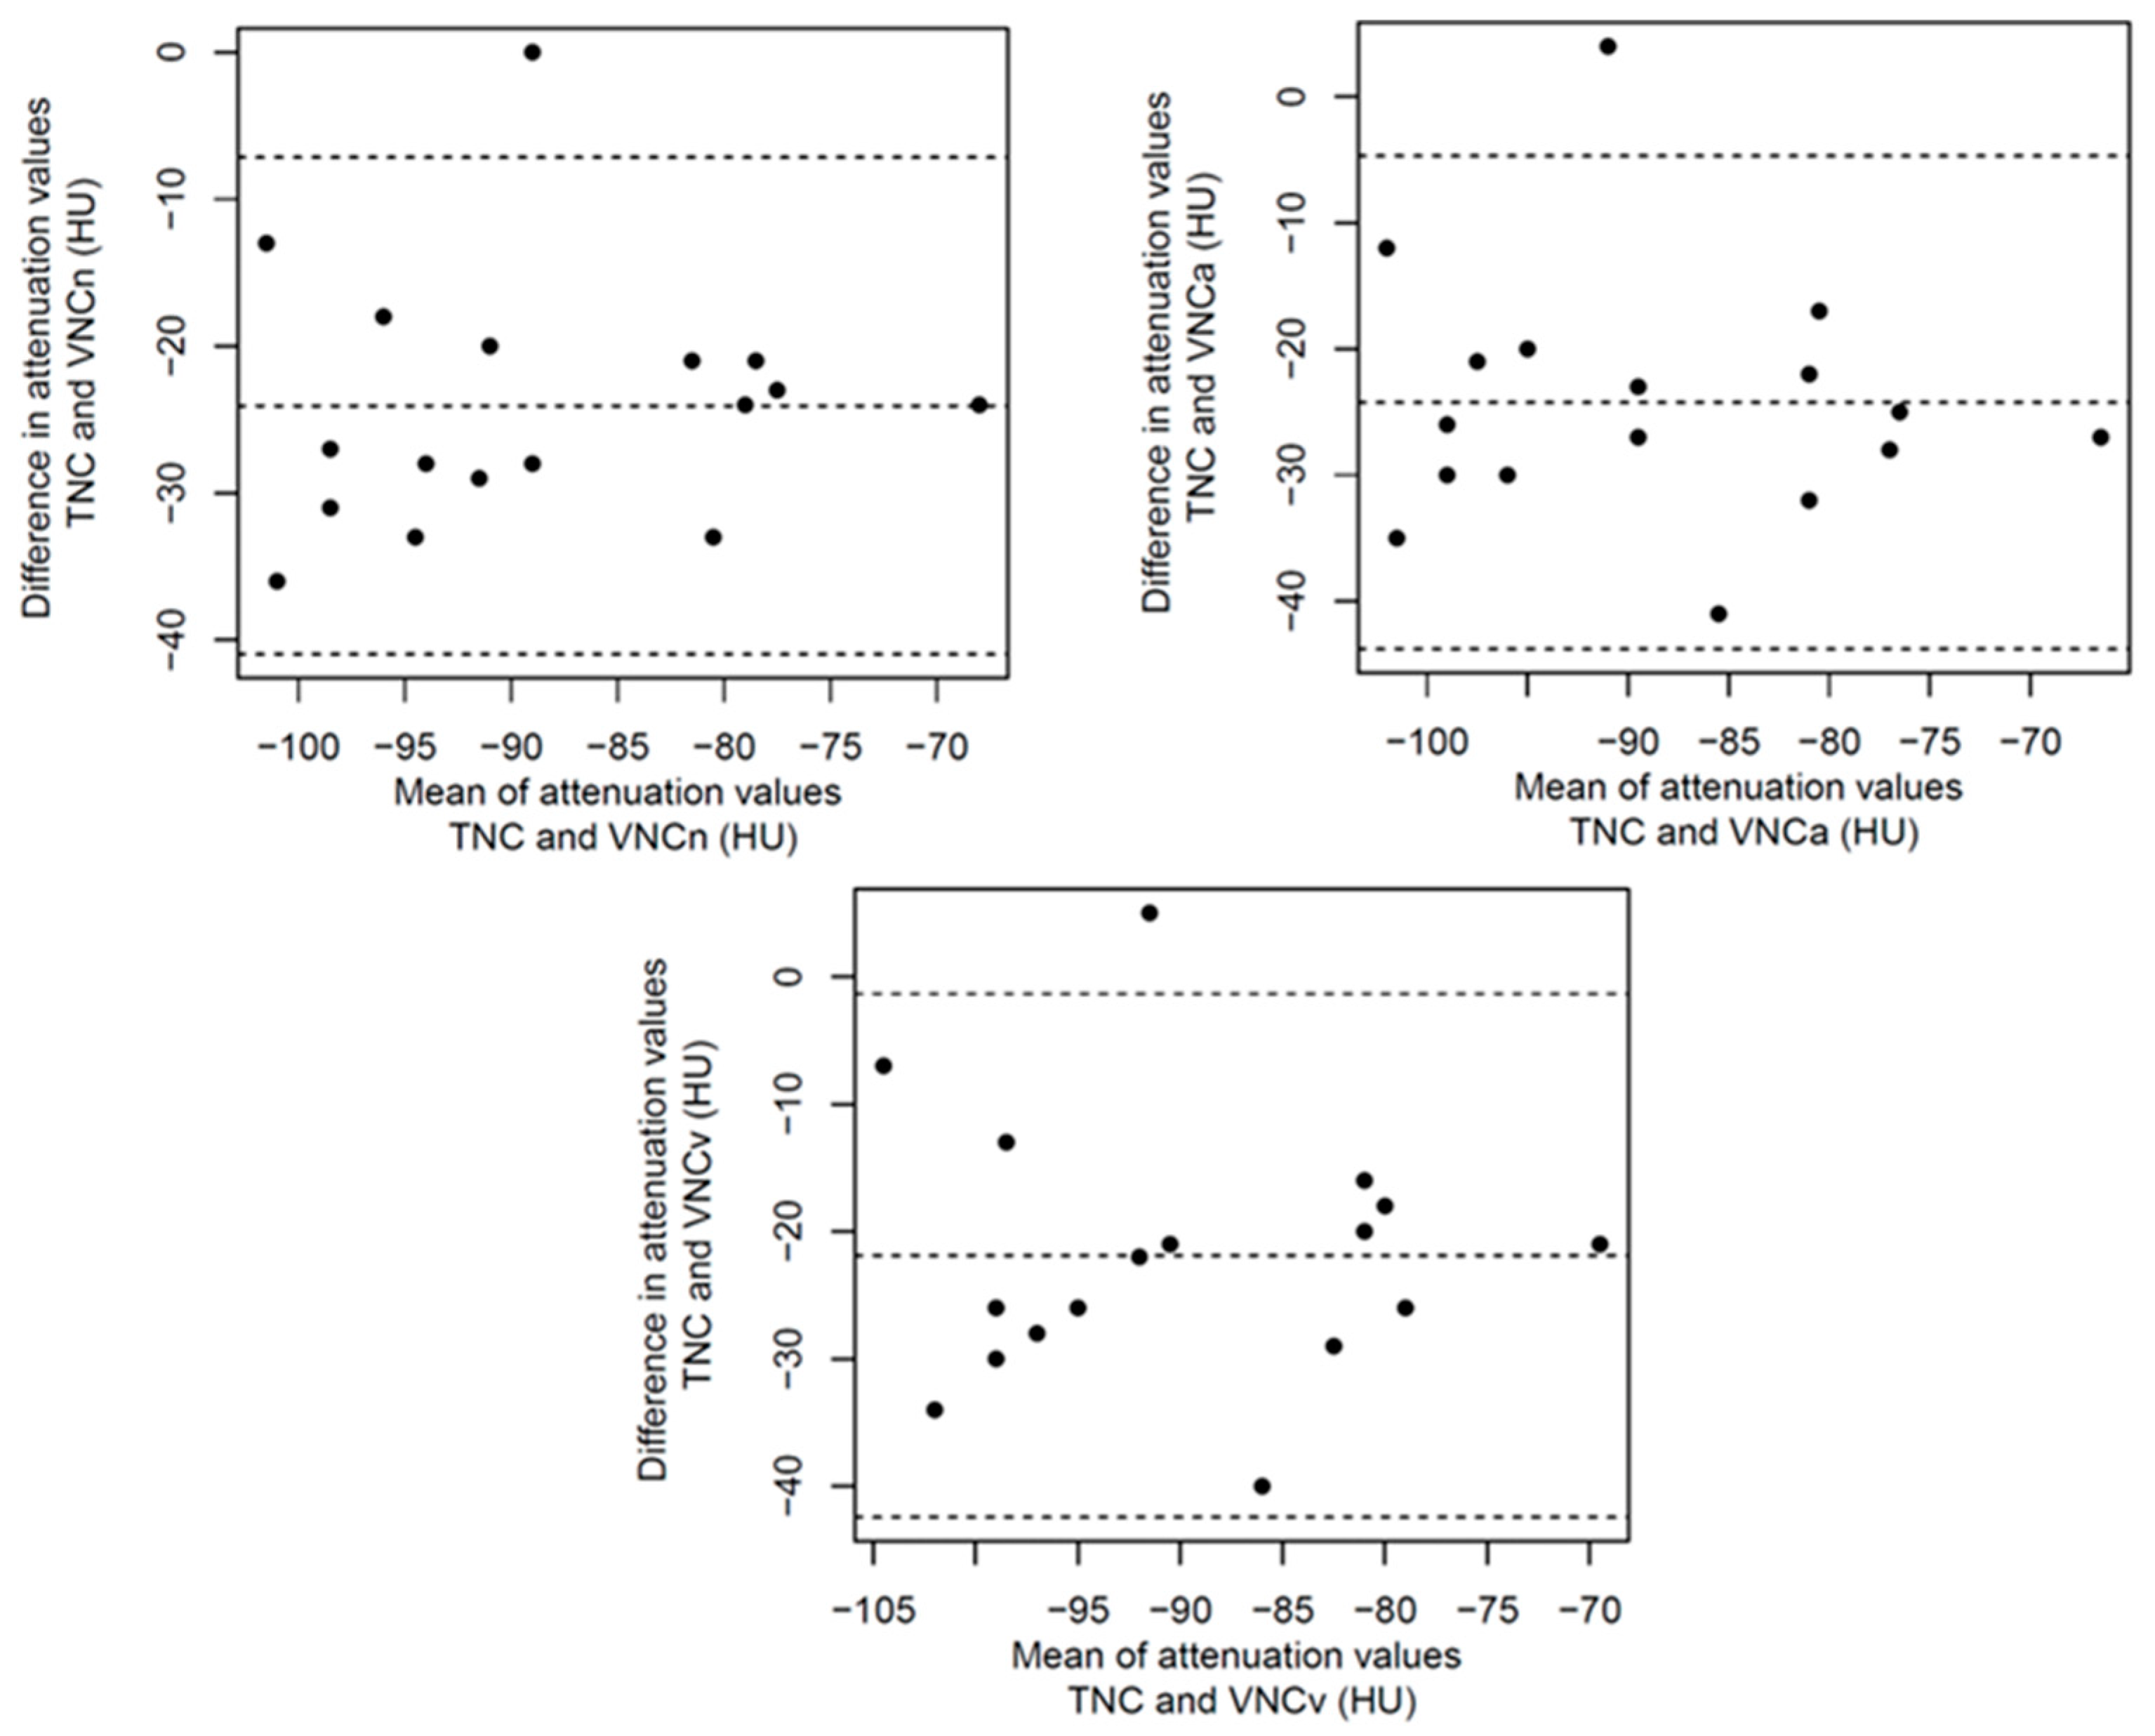

3.2. Structured Measurement